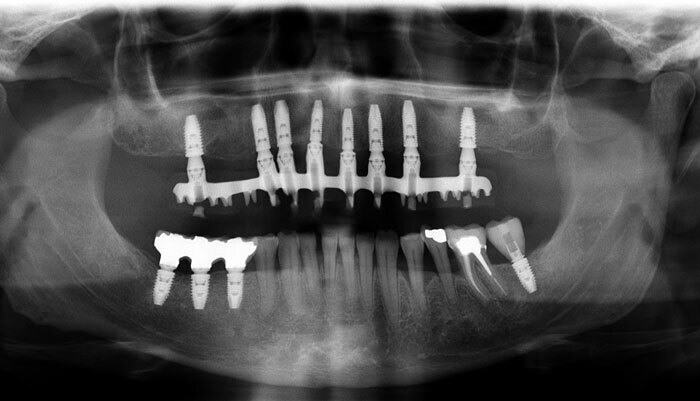

- Cas 6: Greffe du sinus

AVANT : la maladie parodontale a entraîné la perte de toutes les dents maxillaires

APRES : la greffe des deux sinus maxillaires a permis au patient de bénéficier d’une solution FIXE sur 8 implants.